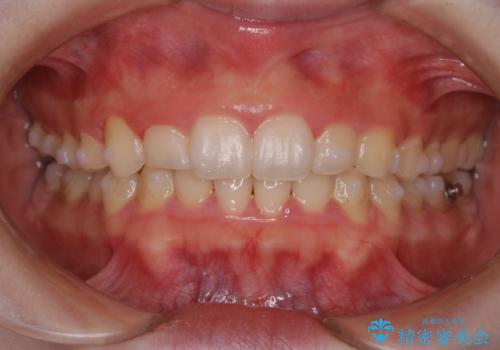

全体的にプラーク(歯垢)付着の患者様(PMTC30分コース)

全体的にプラークが付着していました。

矯正中は、プラークや汚れがとても多く付きやすくなるため、定期的にクリーニングをおすすめします。